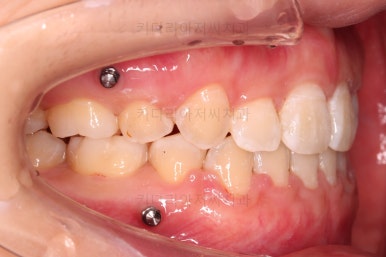

사용한 장치 : 자가결찰 금속(엠파워 메탈, Empower metal) + 미니스크류

초진 시 입안의 모습이에요. 치열이 많이 나쁜 편은 아니고 앞니쪽이 조금 삐뚤어져 있네요.

특히 윗니 작은 앞니 하나가 아랫니보다 안으로 쑥 들어가 있어서 옆에 있는 송곳니가 덧니처럼 보여요.

이번 환자분이 선택하신 장치는 엠파워 메탈이라고 하는 자가결찰 금속장치에요.

철사를 잡아주는(결찰) 뚜껑이 장치에 달려있는 (자가)장치이며, 재질이 금속인 장치에요.

금속 장치는 가장 튼튼하고 부피도 작고 비용도 저렴하다는 장점이 많은 장치입니다.